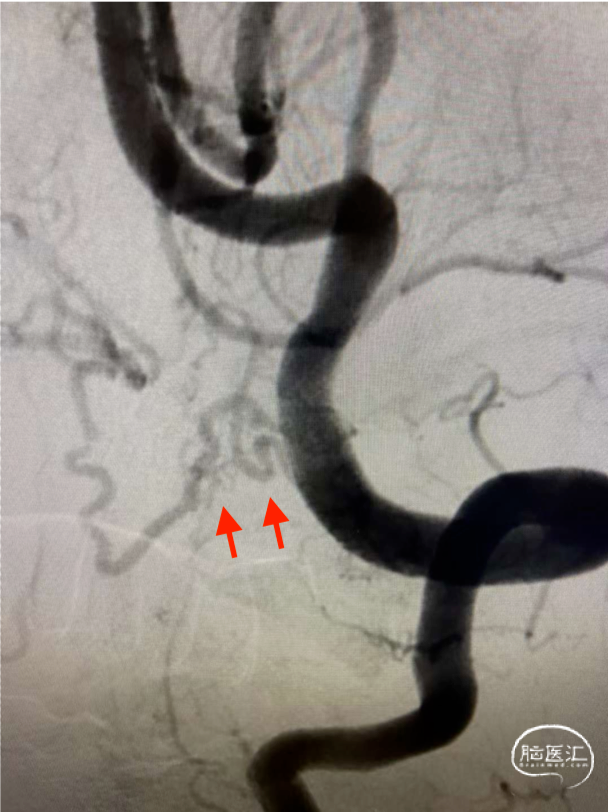

术前DSA

术前正侧位

术前工作位

术前诊断:左侧颅颈交接区硬脑膜动静脉瘘(DAVF)